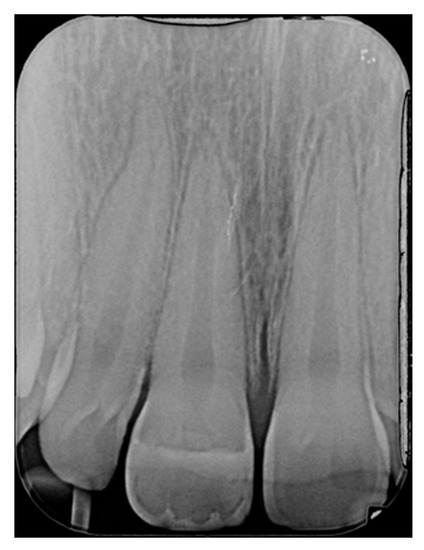

Figure 38.

At 1.5 years, post-operative clinical view. Reprinted from Restauri diretti nei settori anteriori, G. Paolone, S. Scolavino, © 2021, with permission from Quintessence Publishing Italy.

Figure 39.

At 1.5 years, post-operative radiographic view. Reprinted from Restauri diretti nei settori anteriori, G. Paolone, S. Scolavino, © 2021, with permission from Quintessence Publishing Italy.